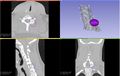

• We have developed a module in Slicer that helps plan the position and orientation of the ice ball for cryotherapy.

• The position, orientation and size of the ice ball can be manually adjusted.

• The user has the choice of three different ice probes - ice ball, ice rod and ice sphere.

• Given the ice ball and the tumor model, the amount of overlap and the distance between the two models can be computed and displayed to the interventionist.

• Automatic estimation of the optimal position and orientation of the ice ball based on BGFS optimization algorithm has been completed.